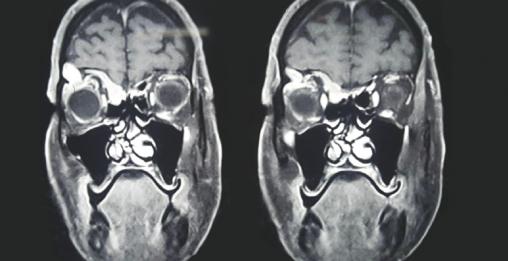

Cet homme de 68 ans consultait pour une énorme mucocèle orbitaire à point de départ ethmoïdal. La symptomatologie clinique était marquée au début par une douleur fronto-orbitaire droite, des troubles visuels, un larmoiement, et une baisse progressive de l’acuité visuelle droite. L’examen ophtalmologique montrait une exophtalmie non inflammatoire non axile et une masse orbitaire refoulant le globe oculaire en bas et en dehors. L’acuité visuelle était à 6/10. L’IRM orbito-cérébrale montrait une masse orbitaire hyperdense, avec destruction du toit de l’orbite et un début d’encéphalocèle (fig. 1). Le kyste était retiré par voie externe (sourcilière) et latéro-nasale droite, mettant en évidence une cavité remplie d’un liquide purulent (fig. 2) dont l’examen cytobactériologique notait la présence de streptocoques. Une antibiothérapie était prescrite. Les suites opératoires immédiates étaient simples, avec régression de la masse orbitaire, avec un recul de 3 ans, par ailleurs le patient ne manifeste aucun signe clinique pouvant évoquer une ré-évolution du pyocéle.